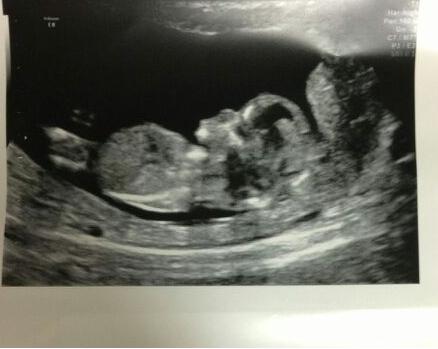

12wk scan pic - gender guess for a friend??

What do you guys think?

Little wee Man!

I'm sorry I can't see a nub.